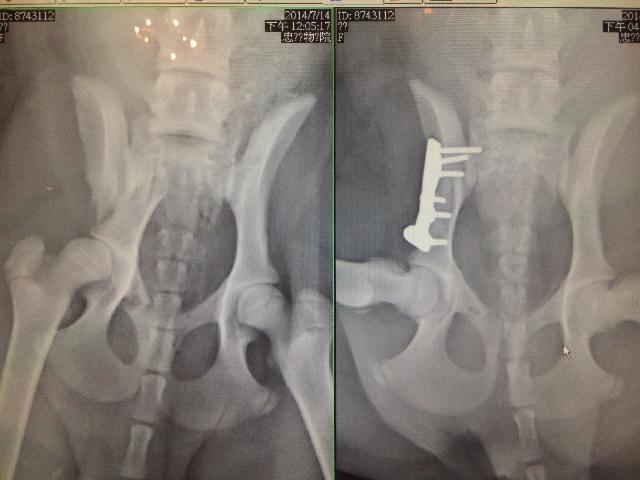

常見的骨骼關節疾病,分下列幾項概述 1. 外力的傷害:車禍或遭受外力的創傷造成的骨折或脫位,可經由放射線(X光)檢查診斷出來。此 種的傷害,大多可經由外科手術來復位。 2. 營養性骨病:幼年犬貓常見的是佝僂病。大多是因為維他命D與鈣攝取不足引起的,這通常與畜主餵養觀念錯誤有關。但另一個原因也不容忽視,就是副甲狀腺功能失調,通常是繼發於高磷低鈣的餵食(如:全肉或餵食大量肝臟),嚴重者甚至可造成病理性骨折,這可以經由詳細的問診及了解餵食方式,再加上放射線檢查來確診。 3. 先天的因素:一般在小型犬較常見的是膝關節異位,尤其以「內側異位」更常見,患犬股骨上的滑車窩較正常犬隻淺,造成膝蓋骨容易脫位。在臨床上,大多是畜主發現後肢不敢著地才就診。 依嚴重程度的不同,可分四級: 第一級:觸診時,可將膝蓋骨撥出,放開時,可自行復位。 第二級:膝關節彎曲時,膝蓋骨會滑出股骨上的滑車窩,將膝關節伸展時,會回到正常位置。 第三級:膝蓋骨大部分的時間在不正常的位置,但仍可用手復位,但彎曲時,又滑出膝蓋骨溝。 第四級:膝蓋骨不在正常的解剖位置,無法再以手復位。 以上第一、二級可先採保守治療,給予疼痛管理,同時可給肌肉鬆弛劑及葡萄糖胺控制,一段時間後,依情況增減藥量。市面上的保健食品很多,畜主可依不同的餵食方式,選擇犬貓適合的產品使用。二級以上可以外科的方式治療。 大型犬大多以髖關節發育不全較常見。尤其是狼犬。此患犬可經由放射線照射檢查出來,在X-光片下可見髖臼窩較正常犬淺,無法正常的包覆股骨頭,因此患犬在行走或奔跑時會跛行或以三隻腳著地。此時才會被畜主發現而就醫。但通常因長期的結構不穩,已經造成髖關節的退行性變化。輕症者可藥物控制及體重控制,重症者可尋求外科的方式治療。